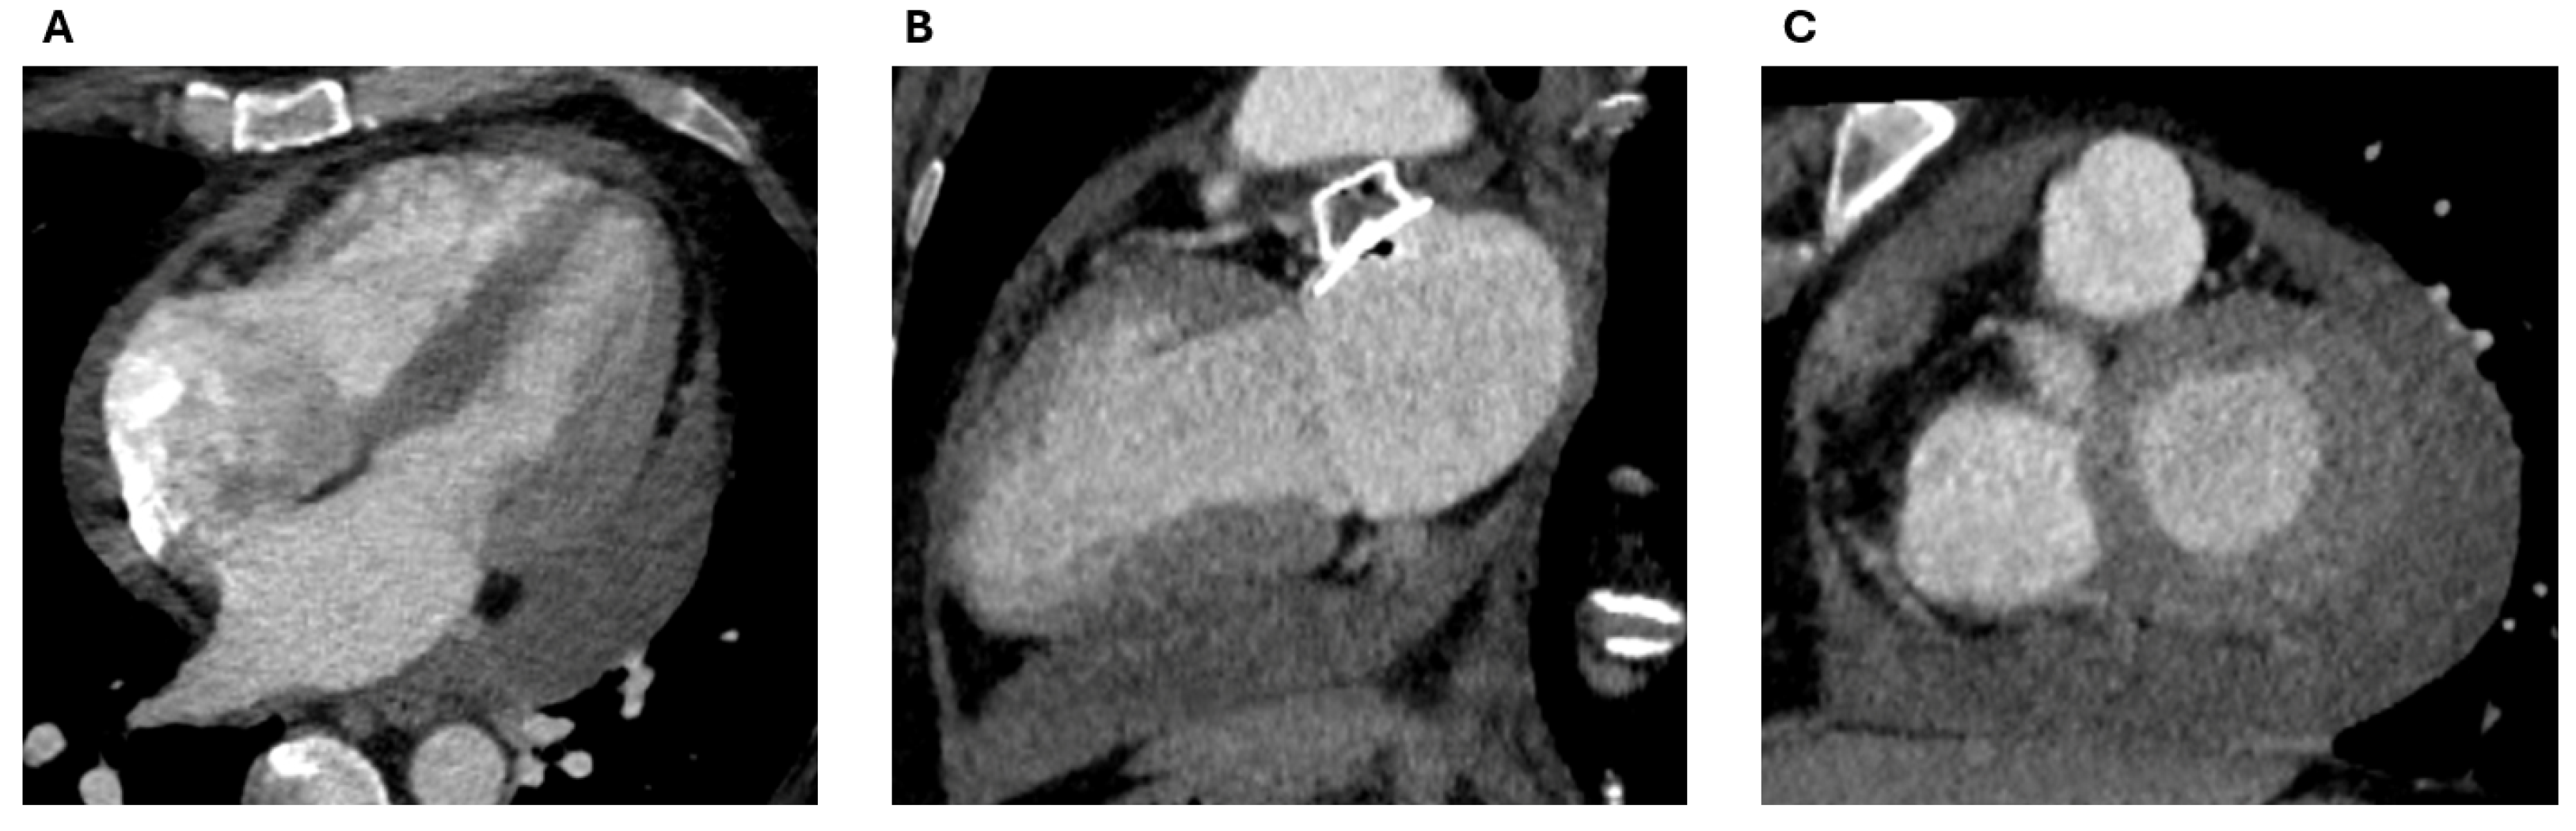

2.1. Cardiac CT

2.1.1. Anatomical Contraindications

2.1.2. LAA Measurements

2.1.3. Assessment of the Inter-Atrial Septum

2.1.4. Other Anatomical Considerations